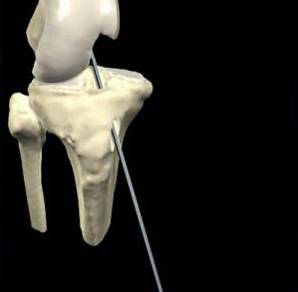

脛骨點(diǎn)選取

股骨點(diǎn)

1.準(zhǔn)確定位,建立骨隧道。